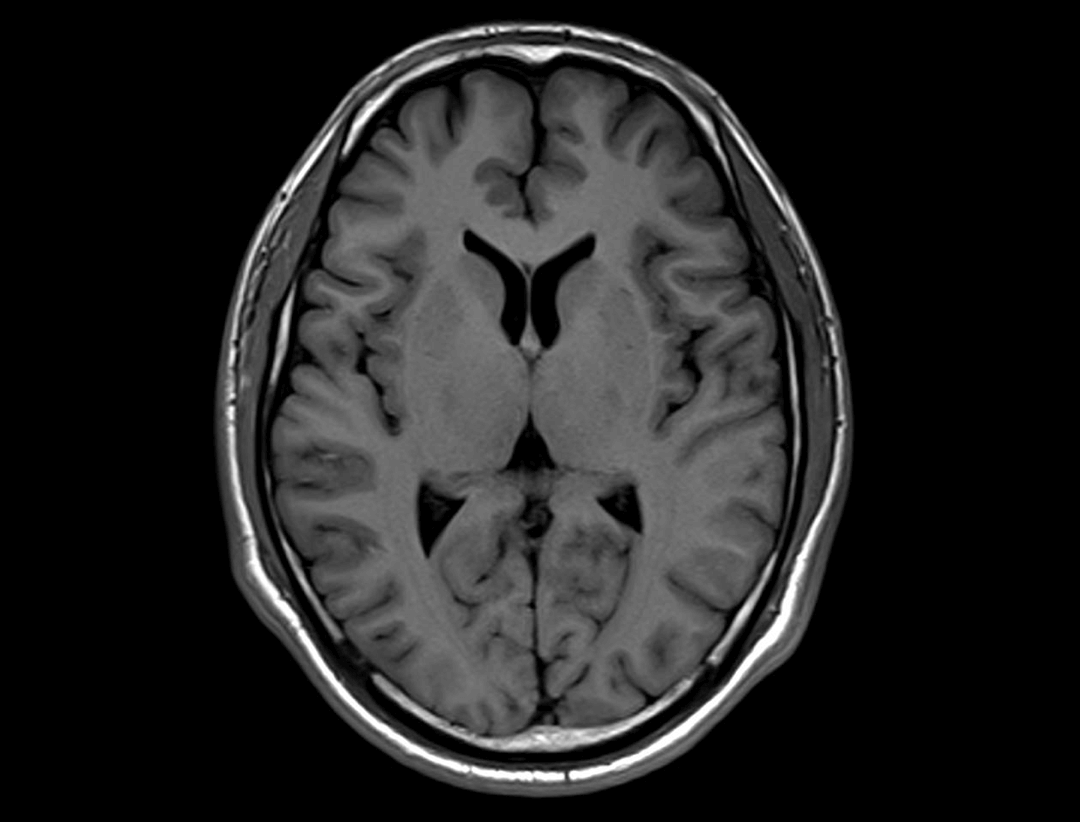

uMR® 770 provides high-speed imaging on all anatomy with significant scan time reduction.

Acceleration technology enables the uMR® 770 to significantly improve scan efficiency and increase patient throughput.